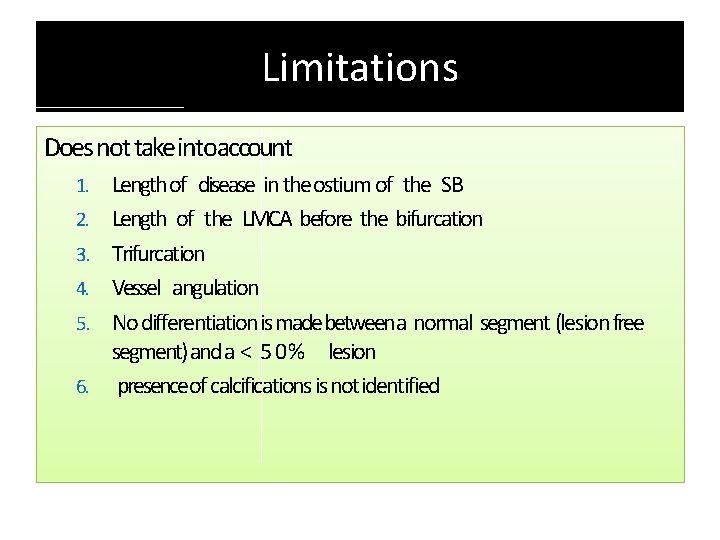

Limitations Does not take intoaccount 1. 2. 3. 4. 5. 6. Length of disease in the ostium of the SB Length of the LMCA before the bifurcation Trifurcation Vessel angulation No differentiation is madebetween a normal segment (lesion free segment) and a < 5 0 % lesion presenceof calcifications is not identified